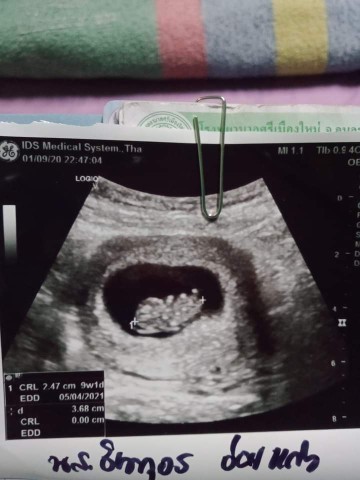

ตอนไปซาวด์ครั้งแรก 9 W ได้ขนาด 2เซนแล้วค่ะ

ตอนซาวด์ครั้งแรก 9วีคค่ะ ได้2เซน

ตอน9 สัปดาห์ค่ะ